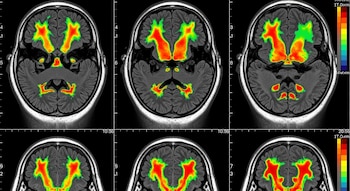

El equipo utilizó imágenes por resonancia magnética funcional y registros directos de actividad cerebral en macacos para identificar las regiones implicadas. Detectaron la corteza motora primaria, la corteza premotora ventral, la corteza cingulada motora y la corteza somatosensorial primaria como partes clave de esta red, según la Universidad Rockefeller.